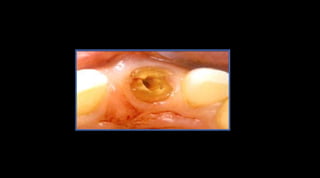

Kantor, M., Pines, M. A comparative study of restorative techniques for pulpless teeth. J. Prost. Dent. (1977) 38:405Consideraciones delos dientes tratados con endodonciaRestauración de un diente tratado endodónticamenteAntes de realizar el tratamiento de endodoncia se debe evaluar la cantidad de tejido dentario remanente que quedará después de la preparación endodóntica

Consideraciones delos dientes tratados con endodonciaDiente con tratamiento endodónticoSolidez EstructuralGrosor mínimo que debe tener un material para evitar su fractura cuando es sometido a una cargaExtensión de la cavidadM-DL-V